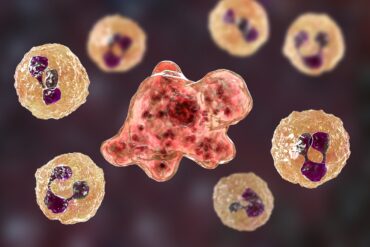

Homem morre após infecção por ameba comedora de cérebro em lago

Um morador do Missouri, nos Estados Unidos, morreu após contrair uma rara infecção cerebral causada pela Naegleria fowleri, conhecida como “ameba comedora de cérebro”. O...